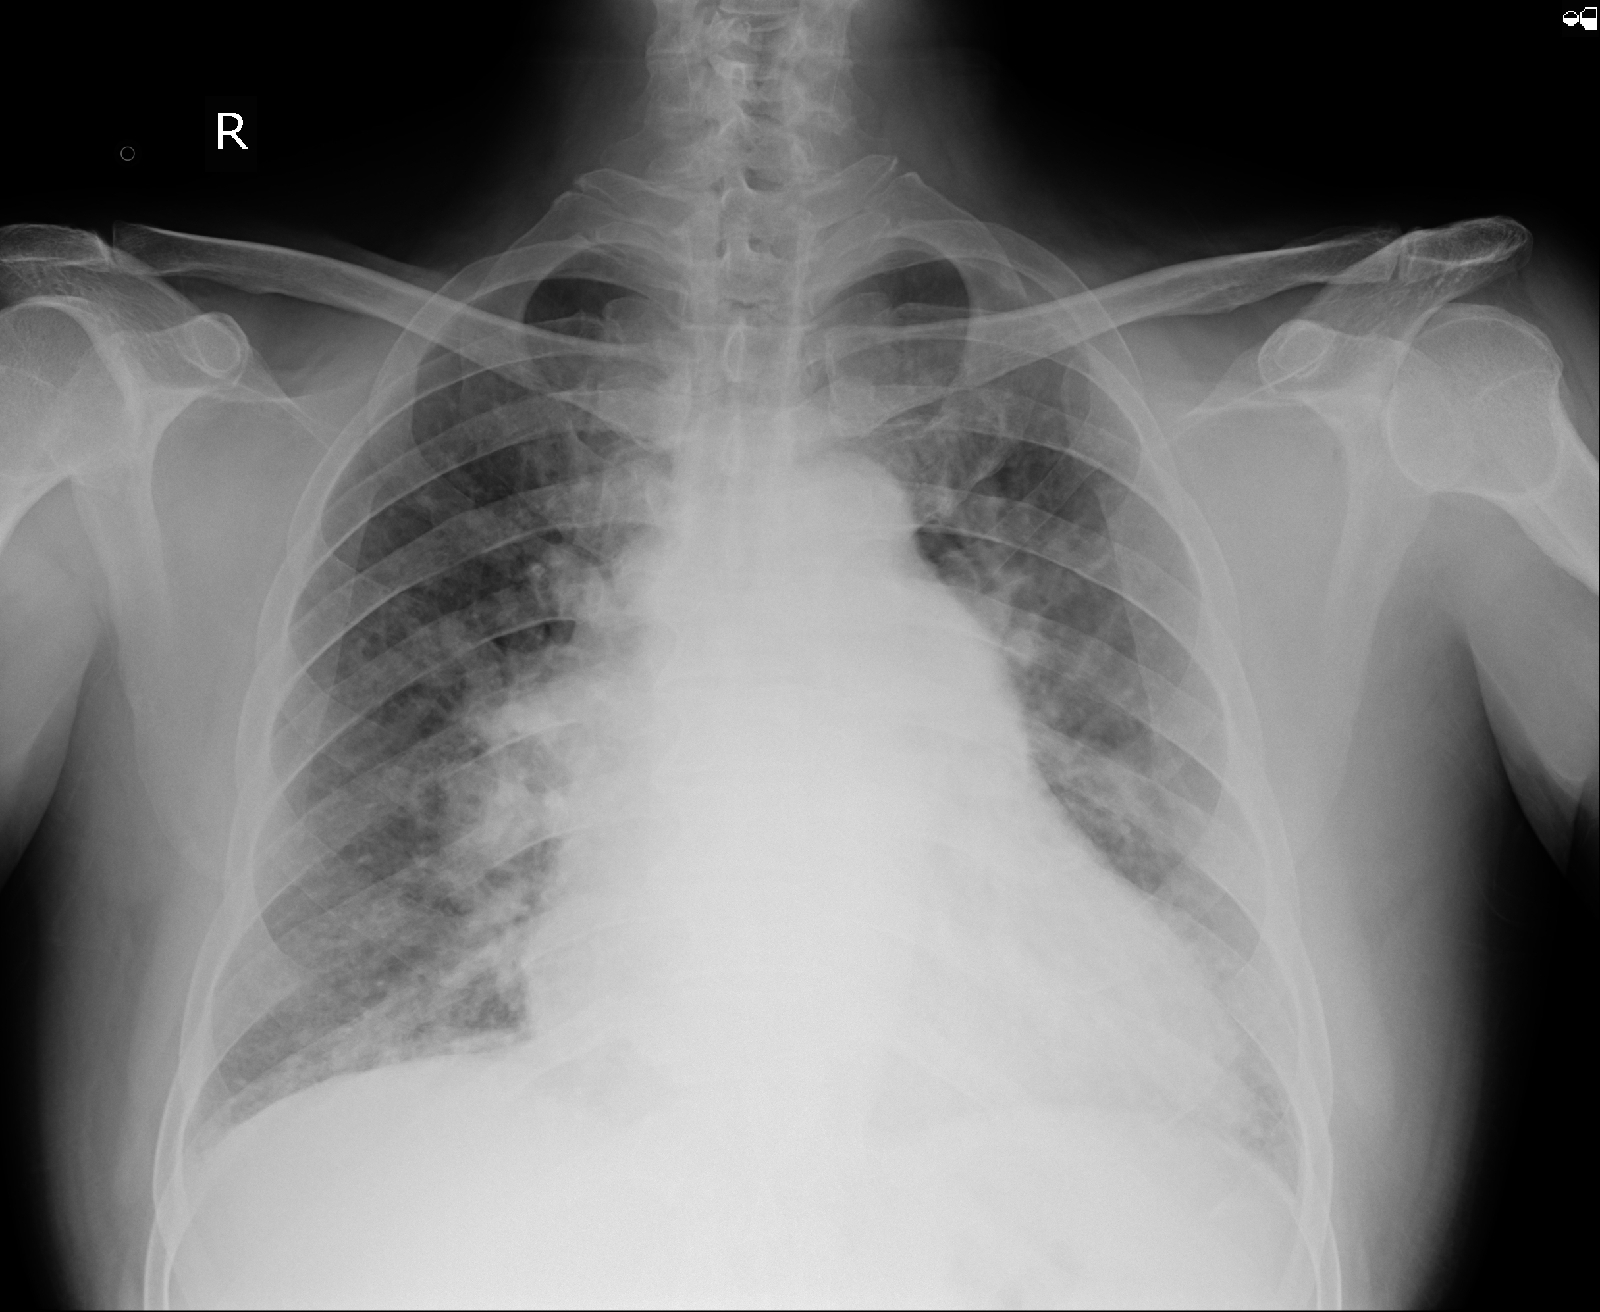

Chest X ray

Diagnosis :

HFpEF with EF -58% Rt.Heart failure secondary to COPD with severe PAH -type 2  with AKI